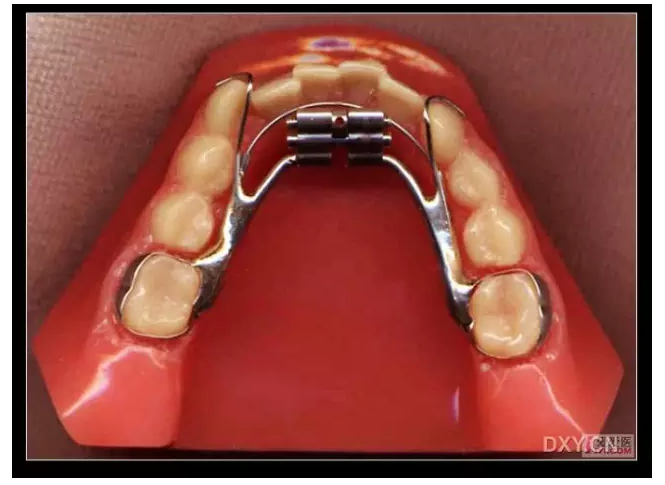

三、擴(kuò)弓器

很多牙列不齊常伴隨牙弓過窄,所以擴(kuò)弓器是正畸醫(yī)生的好伙伴,它可以以多種形態(tài)和您見面。